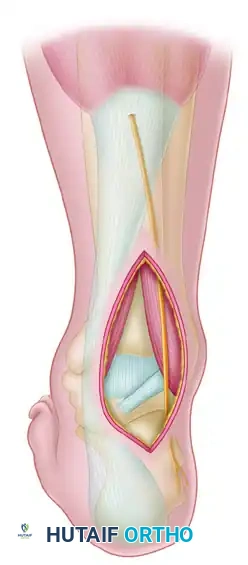

1. The Anteromedial Approach

The anteromedial approach is the workhorse for exposing the medial talar neck and head.

- Incision: Make a 7.5 to 10 cm longitudinal incision beginning proximal and just anterior to the medial malleolus.

- Trajectory: Curve the incision distalward and plantarward toward the sole of the foot, terminating on the medial side of the navicular body.

- Deep Dissection: Develop the interval between the anterior tibial tendon and the posterior tibial tendon.

- Preservation: Expose the fracture and the anteromedial aspect of the neck and body of the talus.

Surgical Warning: Strictly avoid incising the posterior tibial tendon and the neurovascular structures inferior to the medial malleolus. Preserve as much intact soft tissue as possible around the head and neck of the talus to protect the deltoid branches.

Medial Malleolar Osteotomy

If the body of the talus is extruded from the ankle mortise (Hawkins Type III or IV), or if posterior comminution prevents adequate visualization, a medial malleolar osteotomy may be required.

* Pre-drill the medial malleolus for subsequent screw fixation.

* Perform a chevron-type osteotomy directed toward the axilla of the medial clear space.

* Reflect the malleolus inferiorly on its intact deltoid hinge.